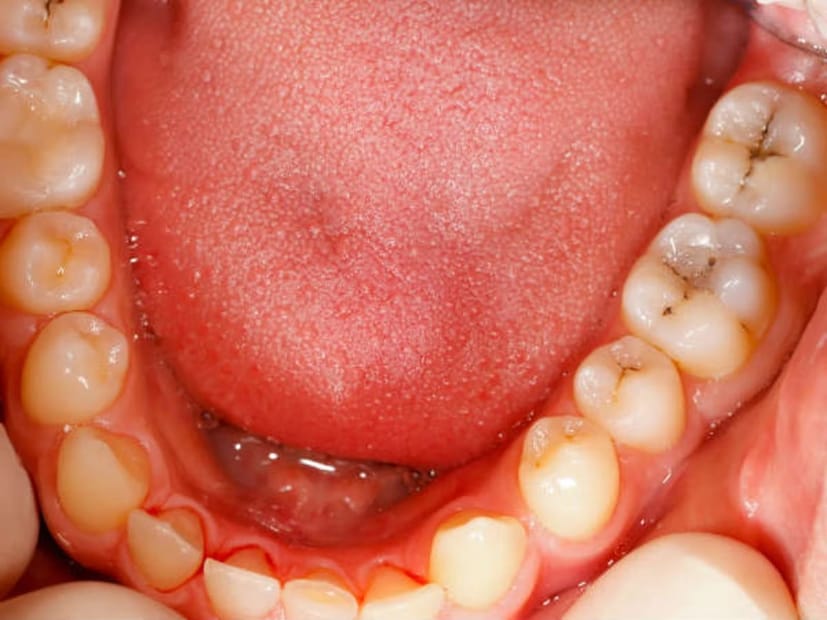

মুখের ক্যানসার আক্রান্তের সংখ্যা দিনে দিনে বাড়ছে। বিশেষ করে স্কোয়ামাস সেল কারসিনোমায় প্রচুর মানুষ আক্রান্ত হচ্ছে। কেন এই সমস্যা, কীভাবে প্রাথমিক অবস্থায় এই থেকে রক্ষা পাওয়া যেতে পারে। এই রোগ মুখগহ্বরে সবচেয়ে বেশি হয়। ইদানীং মুখের ক্যানসারের হার ভয়াবহ আকার ধারণ করছে, মৃত্যুর হারও বাড়ছে। এর অন্যতম কারণ অসচেতনতা।

এই বিষয়ে চিকিৎসক অর্ক ধারার পরামর্শ, জীবনযাত্রার মানের পরিবর্তন ক্যানসার রোগীর সংখ্যা বাড়াচ্ছে। সংখ্যার দিক থেকে আমাদের দেশে নারীদের জরায়ু ও স্তন ক্যানসার এবং পুরুষদের ফুসফুস ক্যানসারের পরই মুখগহ্বরের ক্যানসারের রোগী বেশি দেখা যায়। যাঁরা মুখের ক্যানসারে আক্রান্ত হন, তাঁদের বেশির ভাগের বয়স ৪০ বছরের বেশি। নারীদের তুলনায় পুরুষেরাই এই ক্যানসারে আক্রান্ত হন বেশি।